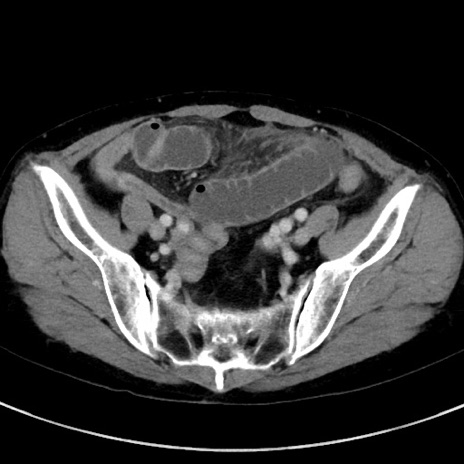

症例23(横断像)

【症例】70歳代女性

【主訴】下腹部痛・嘔吐

【現病歴】2日前より腹痛あり。昨日嘔吐あり。症状改善しないため来院。

【既往歴】胃GISTに対して胃部分切除後。

【身体所見】BT 37.1℃、BP 128/77mmHg、腹部:平坦・軟、下腹部に圧痛あり。

【データ】WBC 10200、CRP 0.31